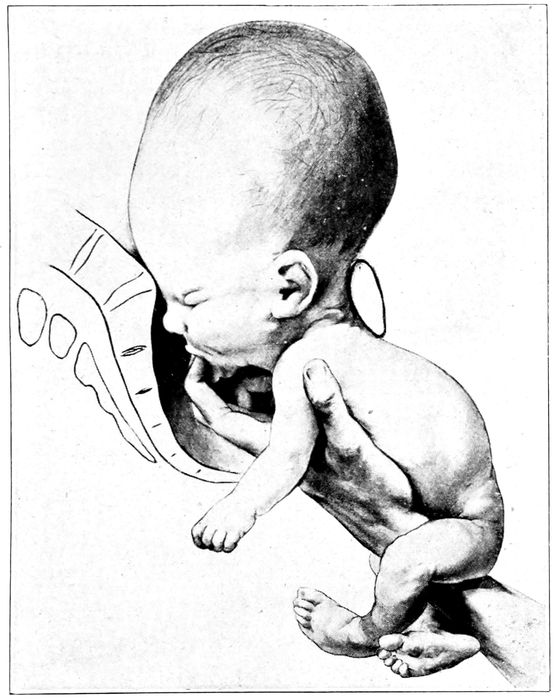

Fig. 20.—Normal attitude of fœtus (complete flexion). (Barbour.)

During development, the movements of the child become

observed. Gradually the child assumes a definite attitude

in the uterus. It becomes more and more folded

and flexed to accommodate its size to the limitations of

space. The head bends on the chest, the arms are

folded, the thighs flex against the abdomen, the legs

on the thighs, and even the back ultimately becomes

convex. It attains a complete flexion, the normal attitude

of the child. As maturity approaches, the head

becomes more and more palpable and seeks its usual location

in the lower pole of the uterus, resting on the

pelvic brim.